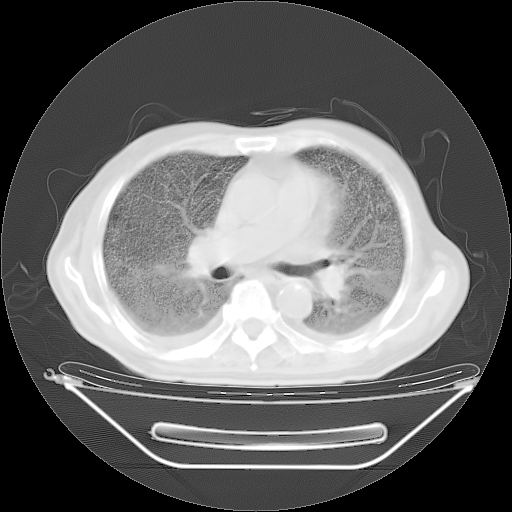

胸腹部CT,诊断意见:左上肺叶钙化灶、左侧胸膜局限性增厚并钙化、胆囊炎。描述部分肺组织呈磨玻璃样改变。